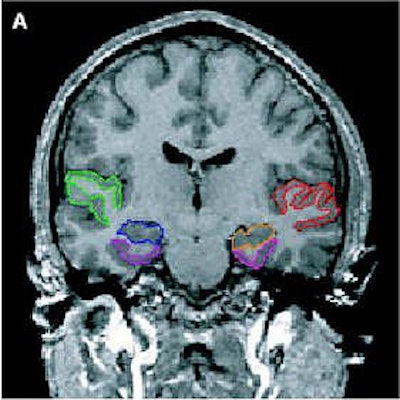

| Above, regions of interest (ROI) examined in MRI study of patients with first-episode schizophrenia or affective psychosis and normal comparison subjects. Top (A) is a 1.5-mm coronal slice of the temporal lobe; the ROI used to evaluate the temporal structures are outlines. The gray matter of the superior temporal gyrus is shown in red (subject left) and green (subject right); more medially, the amygdala-hippocampal complex is shown in orange (left) and blue (right) with the parahippocampal gyrus underneath in pink (left) and purple (right). Below, a left lateral view of a 3D reconstruction of the cortical surface with the anterior superior temporal gyrus (light pink) and posterior superior temporal gyrus (red). |